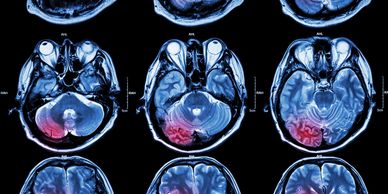

A proper diagnosis is crucial. Medical professionals typically conduct a physical examination and, if necessary, may request imaging such as ultrasounds or MRIs to assess the severity of the contusion.